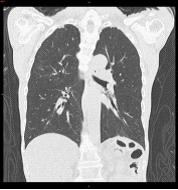

CTは2012年3月にAquilion ONE (320列CT)、 MRIは2014年2月に ECHELON OVAL (1.5T )が導入されました。320列CTは被ばく低減技術 AIDR3Dを使用することで通常のCT検査のみならず、CT検診も 大幅な被ばく低減 が可能となりました。大腸CT検診、肺がんCT検診では従来の1/5~1/10線量で検査をしています。

2012年4月には東北初となる、大腸CT検診もスタートしました。320列CTを使用し、ギリギリまで被ばく線量を下げた大腸CT検診、肺がんCT検診、心臓ドックを行っています。是非この機会に当院のCT検診をご利用ください。